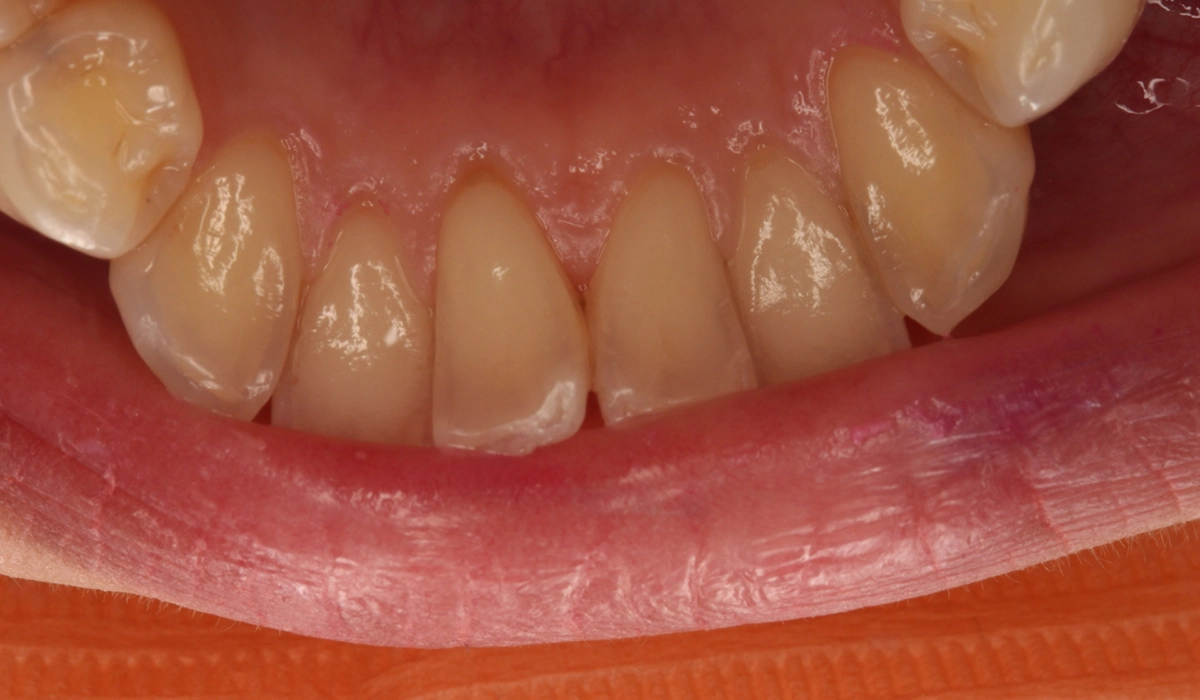

術後:前歯部あおり

術後:オーバージェット